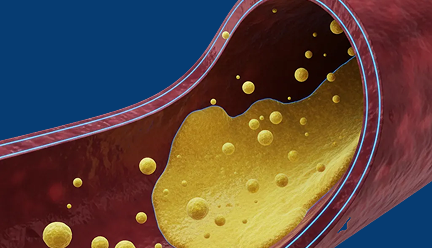

1

고혈압, 당뇨, 고지혈증 약을 복용 중이다.